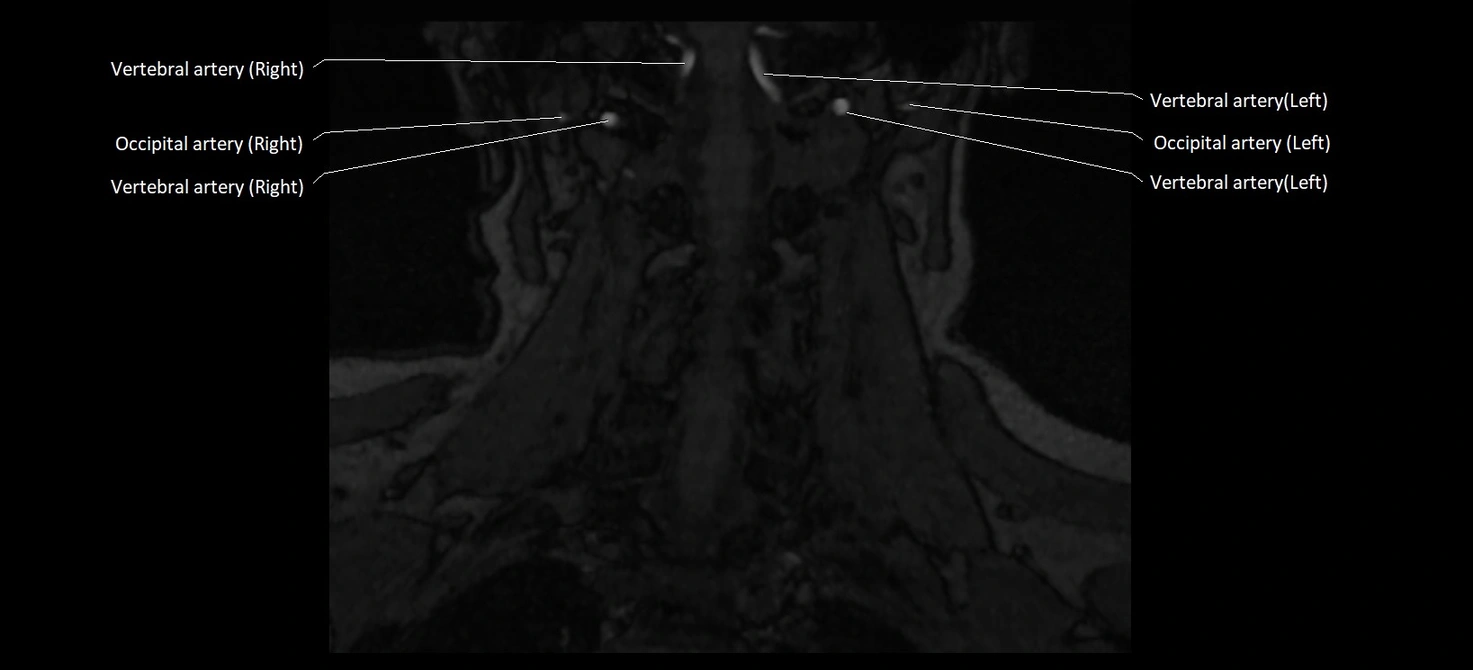

MRI images

image